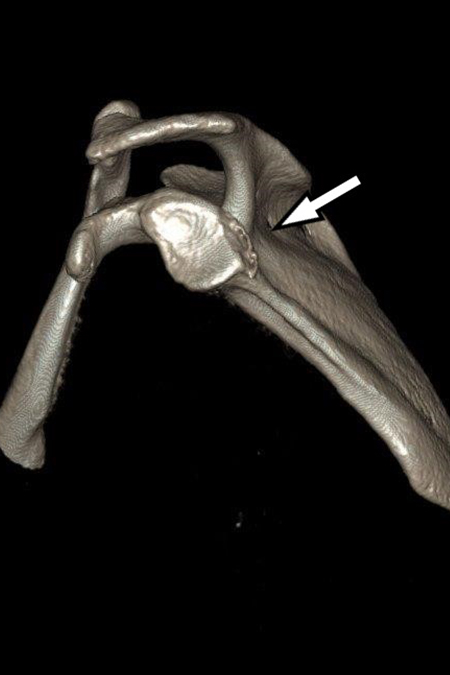

34 Jährige Patientin mit chronischer rechter Schulterinstabilität nach vorne unten. Bei der Analyse des Gelenkes fand sich in der 3D Schichtbilduntersuchung ein knöcherner Defekt (12% des Durchmessers) am vorderen unteren Pfannenrand. Operatives Vorgehen mit Spanaufbau des Defektes vom gleichseitigen Beckenkamm und Kapselstabilisation. Der Span wurde mit bioresorbierbaren Schrauben fixiert. Nach 3 Monaten bereits sehr gutes stabiles Bewegungsbild bei eingeheiltem Span. Noch Kraftaufbau erforderlich.

VORDERE CHRONISCHE SCHULTERINSTABILITÄT – KNÖCHERNER DEFEKT

Knöcherner Defekt am unteren Pfannenrand

Knöcherner Defekt durch Span ausgeglichen